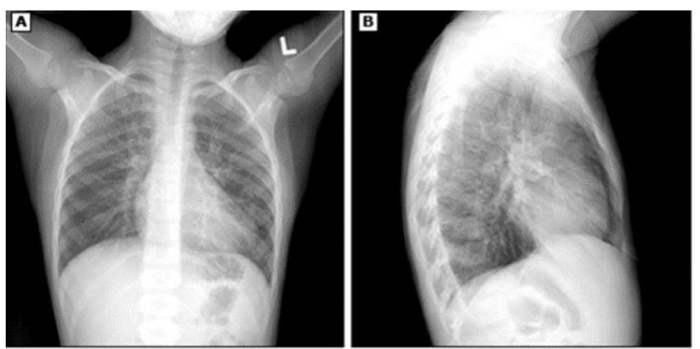

A radiografia de tórax PA e perfil são indicados para todos os pacientes que apresentam suspeita de

Pneumonia Adquirida na Comunidade (PAC) além de auxiliar no diagnóstico ajuda a identificar a

presença de outras complicações relacionadas à patologia de base.

A imagem abaixo reflete como principal achado: